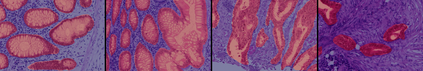

Weakly-supervised learning (WSL) has recently triggered substantial interest as it mitigates the lack of pixel-wise annotations. Given global image labels, WSL methods yield pixel-level predictions (segmentations), which enable to interpret class predictions. Despite their recent success, mostly with natural images, such methods can face important challenges when the foreground and background regions have similar visual cues, yielding high false-positive rates in segmentations, as is the case in challenging histology images. WSL training is commonly driven by standard classification losses, which implicitly maximize model confidence, and locate the discriminative regions linked to classification decisions. Therefore, they lack mechanisms for modeling explicitly non-discriminative regions and reducing false-positive rates. We propose novel regularization terms, which enable the model to seek both non-discriminative and discriminative regions, while discouraging unbalanced segmentations. We introduce high uncertainty as a criterion to localize non-discriminative regions that do not affect classifier decision, and describe it with original Kullback-Leibler (KL) divergence losses evaluating the deviation of posterior predictions from the uniform distribution. Our KL terms encourage high uncertainty of the model when the latter inputs the latent non-discriminative regions. Our loss integrates: (i) a cross-entropy seeking a foreground, where model confidence about class prediction is high; (ii) a KL regularizer seeking a background, where model uncertainty is high; and (iii) log-barrier terms discouraging unbalanced segmentations. Comprehensive experiments and ablation studies over the public GlaS colon cancer data and a Camelyon16 patch-based benchmark for breast cancer show substantial improvements over state-of-the-art WSL methods, and confirm the effect of our new regularizers.